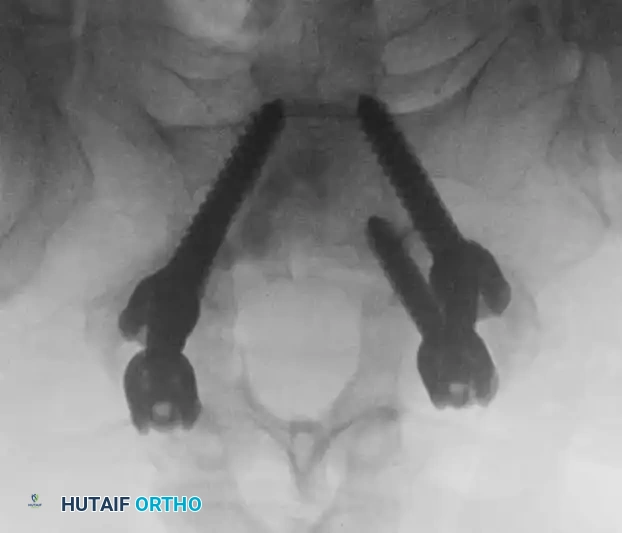

5. Pedicle Screw Instrumentation and Fluoroscopic Verification

• Pedicle screws are placed bilaterally into the cephalad and caudal vertebrae. The entry point is typically at the intersection of the pars interarticularis, the superior articular facet, and the transverse process.

• The pedicles are cannulated with a gearshift probe, palpated with a ball-tip feeler to ensure no cortical breaches, tapped, and the screws are inserted.

• Intraoperative fluoroscopy is absolutely critical during this phase to confirm trajectory and depth.

Image

Intraoperative AP fluoroscopy demonstrating the initial placement and medial trajectory of the pedicle screws within the vertebral bodies.

Alternative AP fluoroscopic view confirming bilateral symmetry and appropriate convergence of the pedicle screws, ensuring they do not breach the medial pedicle wall into the spinal canal.

• Once screw placement is confirmed, titanium or cobalt-chrome rods are contoured to match the patient's natural lumbar lordosis and secured to the screw heads with set screws.

• Compression is applied across the construct to load the interbody cage, adhering to Wolff's Law to promote osteogenesis.